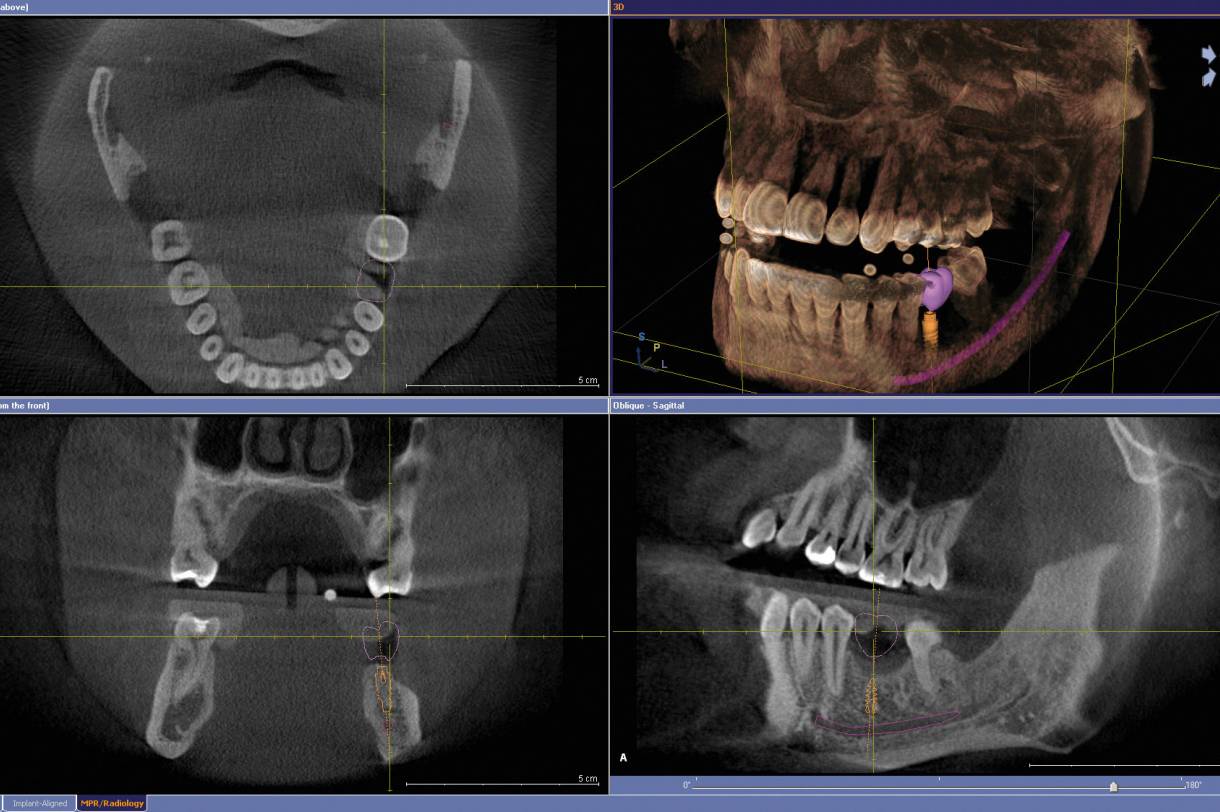

Durch die dreidimensionale Darstellung der Kiefer, Kiefergelenke, Nasennebenhöhlen und Zähne, eröffnen sich völlig neue Möglichkeiten. Operative Eingriffe im Kiefer-Gesichtsbereich sowie im Bereich der Nasennebenhöhlen können nun virtuell am Computer simuliert und damit extrem zielgerichtet, oftmals minimalinvasiv und maximal patientenschonend durchgeführt werden.

- Zahnimplantaten, durch computergestützte 3D - Präzisionsplanung und Navigation, die den medizinischen Eingriff schnell, schonend und um ein Vielfaches sicherer und genauer als konventionelle Implantationen möglich machen